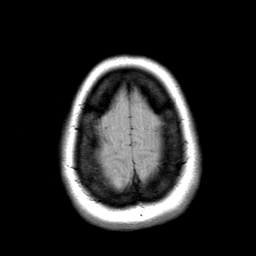

Cerebral hemorrhage, MR Study mr-pd -- Slice #21

[Home][Help][Clinical] Slice 21